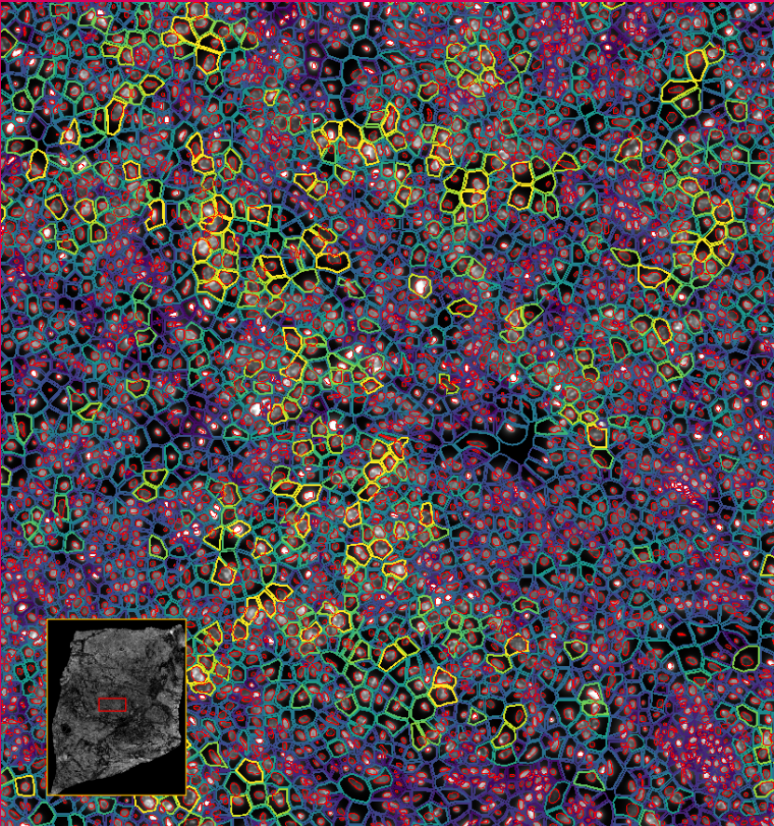

ͼ2£ºXeniumÊý¾Ý¸ÅÀÀ

ͼ3£ºXenium½«¹âÑ§ÌØÕ÷½âÂëΪת¼±¾±í´ï£¬ÊÕÂÞ²¢ÐγÉͼÏñ

ͼ4-1£ºÊ¹ÓÃDAPI¶Ôϸ°ûºËȾɫ£¬ÍŽáÉî¶ÈѧϰҪÁìÍÆ¶ÏÍêÕûµÄϸ°û½çÏß

ͼ4-2£ºÊ¹ÓÃDAPI¶Ôϸ°ûºËȾɫ£¬ÍŽáÉî¶ÈѧϰҪÁìÍÆ¶ÏÍêÕûµÄϸ°û½çÏß